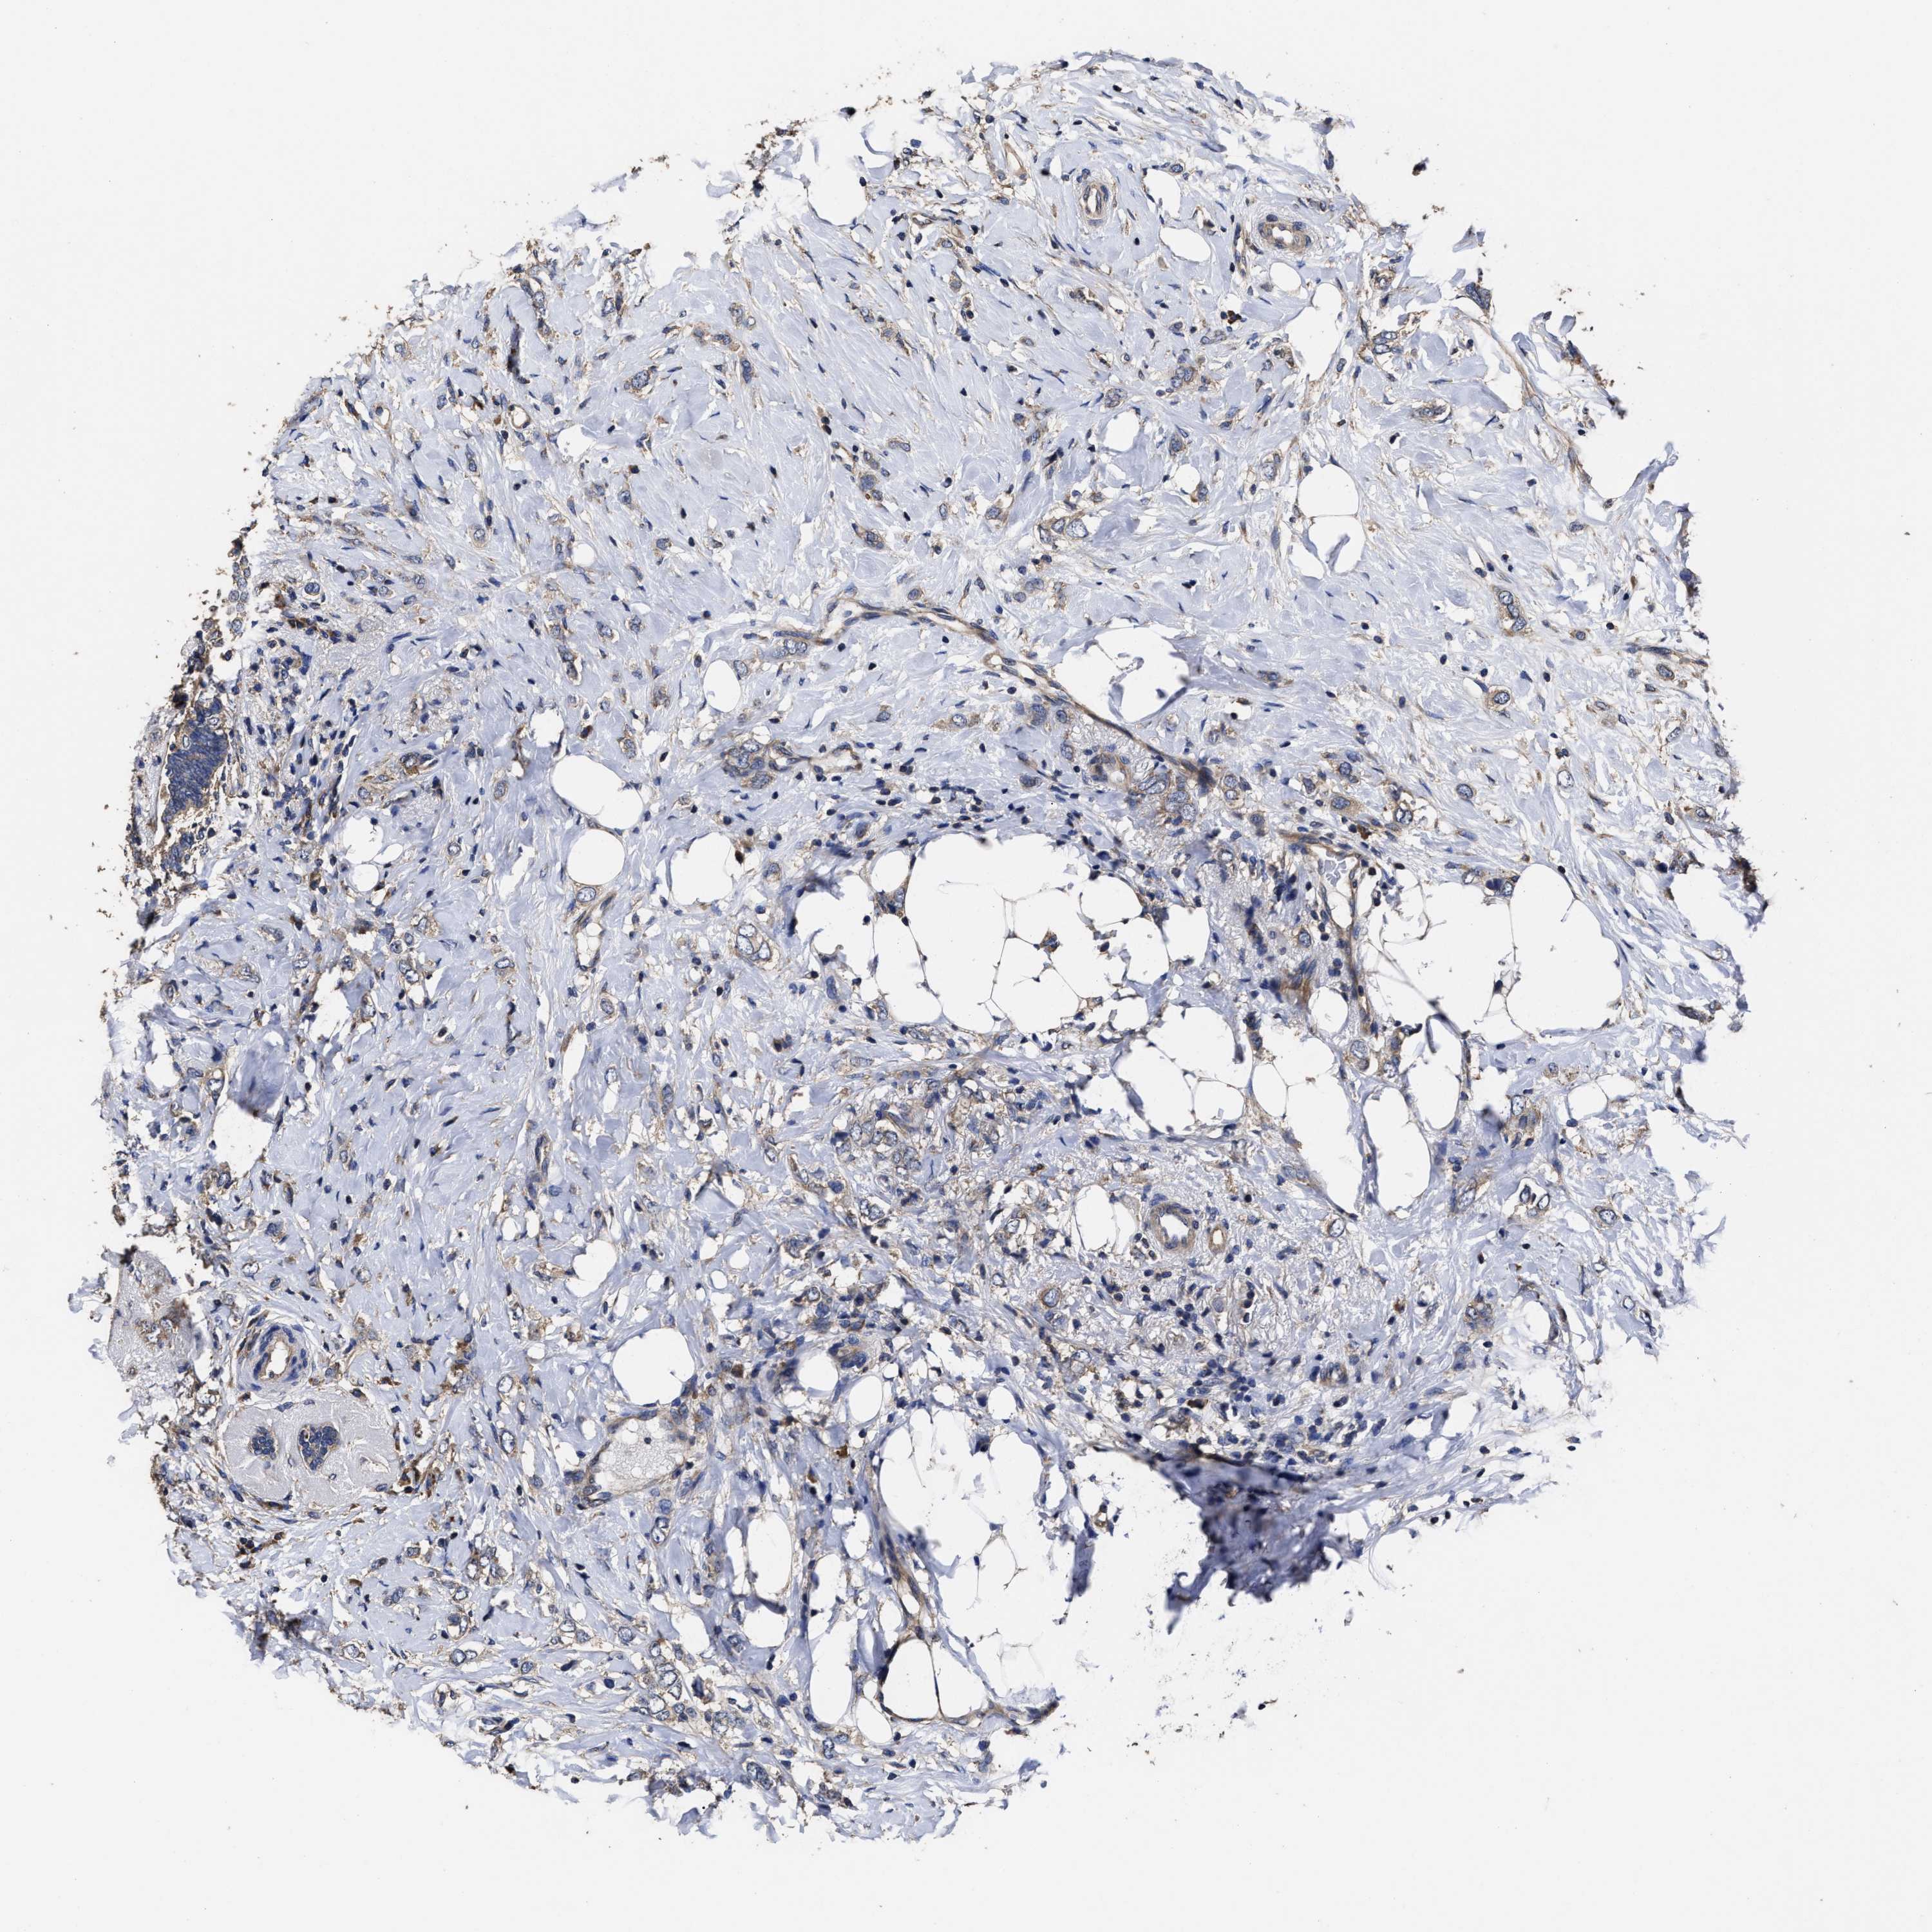

CANCER BREAST CANCER Show tissue menu

BRCA TCGA BRCA VALIDATION PROTEIN EXPRESSION